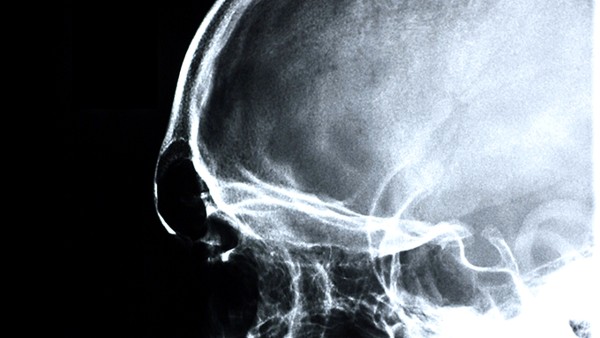

腦萎縮是老年人常見(jiàn)的疾病,一般是退行性疾病引起的。如果治療不好,甚至?xí)?dǎo)致記憶力明顯下降,導(dǎo)致患者無(wú)法照顧自己。所以要及時(shí)去醫(yī)院檢查,通過(guò)藥物治療及時(shí)改善病情,避免腦萎縮引起的嚴(yán)重并發(fā)癥。